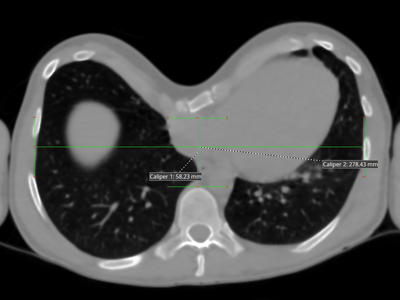

Illustration of the calculation of the Haller index of a Pectus

The Haller index was established in 1987 to assess the scale of a Pectus based on a calculation made on a digital image. It is established from a CT scan at the level of the deepest point of the depression: it is the ratio of maximum width and depth.

The Haller index allows measurement of the defect and funnel depth especially in women where the deformation is hard to evaluate because of the breast volume. The higher the Haller index, the deeper the Pectus Excavatum.

It is practical and still used, but it gives an imperfect idea of the importance of the depression and does not prejudge any possible and rare functional impact of the concave chest.